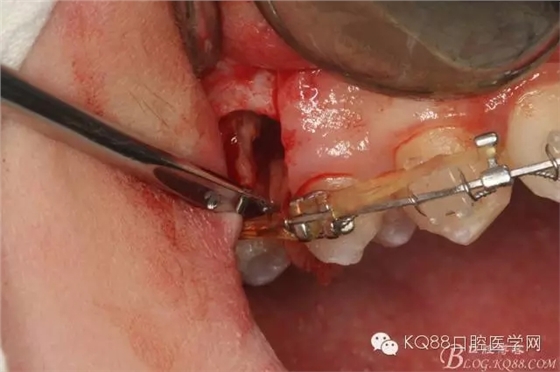

圖11.仔細考慮之后,在14頰側(cè)做垂直切口,切口長度僅達膜齦聯(lián)合處,做小切口。

圖12. 做垂直切口+齦溝內(nèi)切口,形成角形瓣,暴露出15根面。